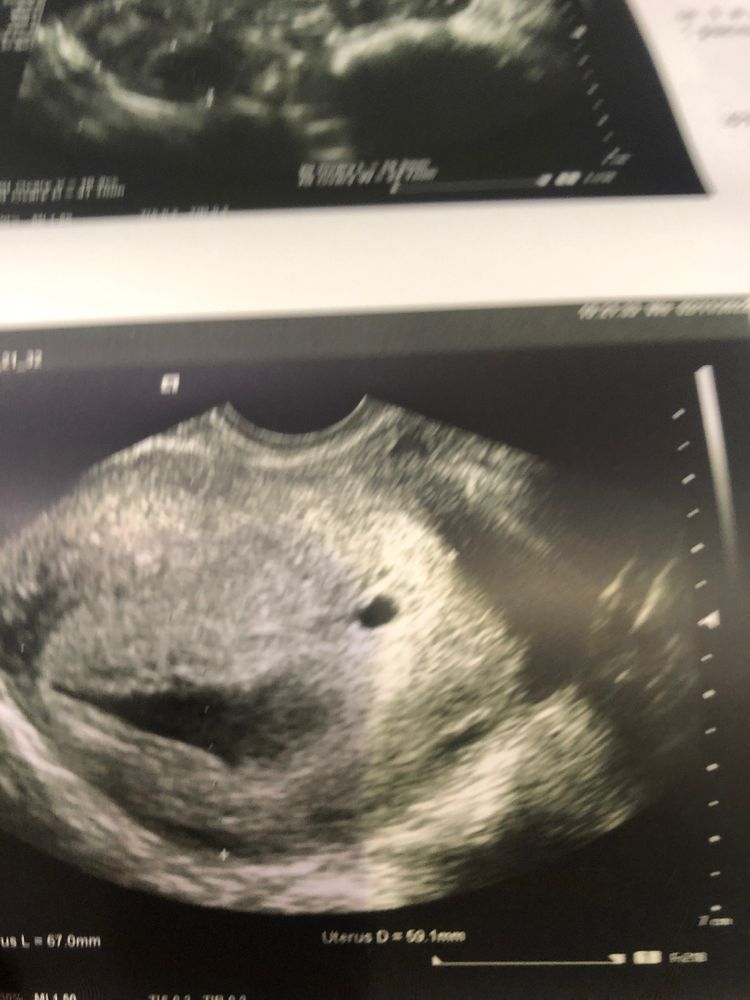

Оксана, что у вас в итоге? Оба развиваются? У меня тоже два пя было на прошлом узи, но одно меньше гораздо и сказали скорее всего рассосется. Вот через неделю иду на узи повторно. Очень хочу двойню.

Моя первая беременность (моно ди двойня) Беременность двойней после трёх кесаревых. После последнего КС прошло полгода.